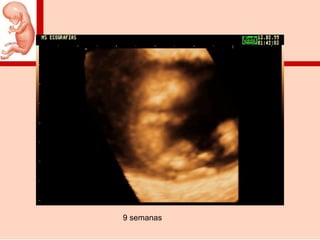

9 semanas